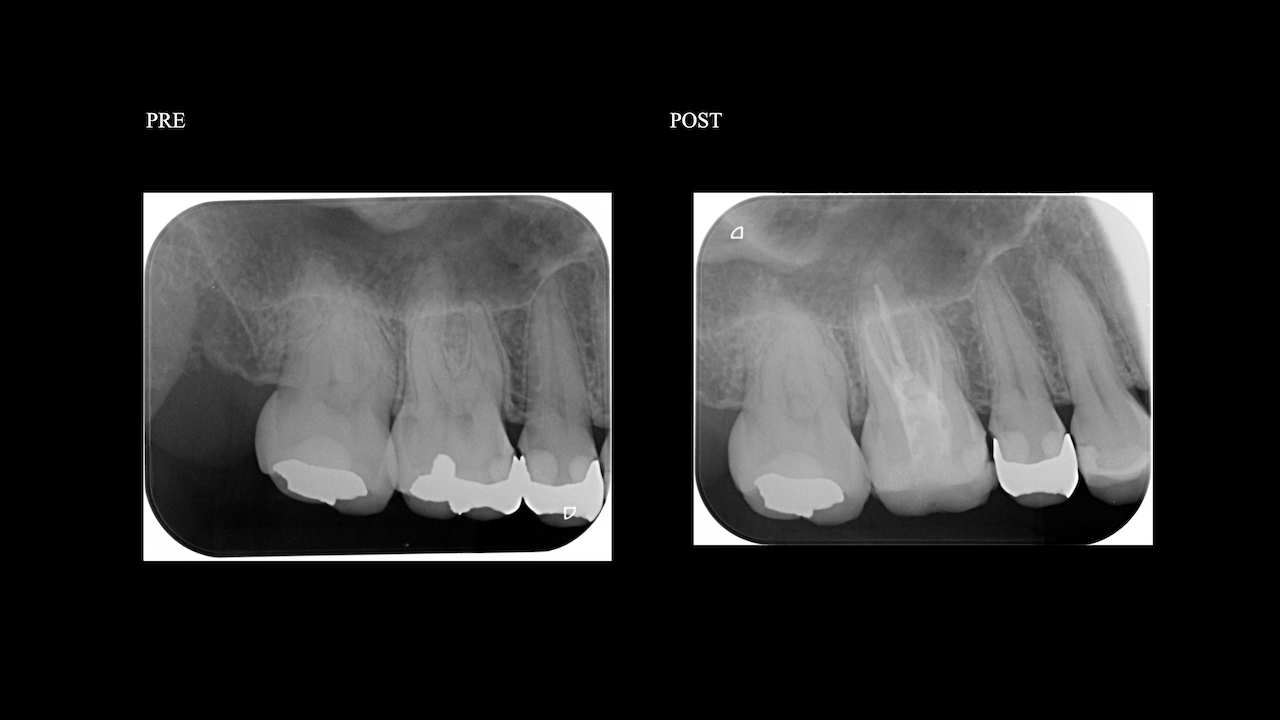

アンダー根管形成を疑い、K先生は再治療した。

すると…

10年もののSinus tractが再根管治療で消失した。

もう1ケースが以下だ。

この患者さんも長いSinus tractを有していたにも関わらず、再根管治療でその臨床症状は消失した。